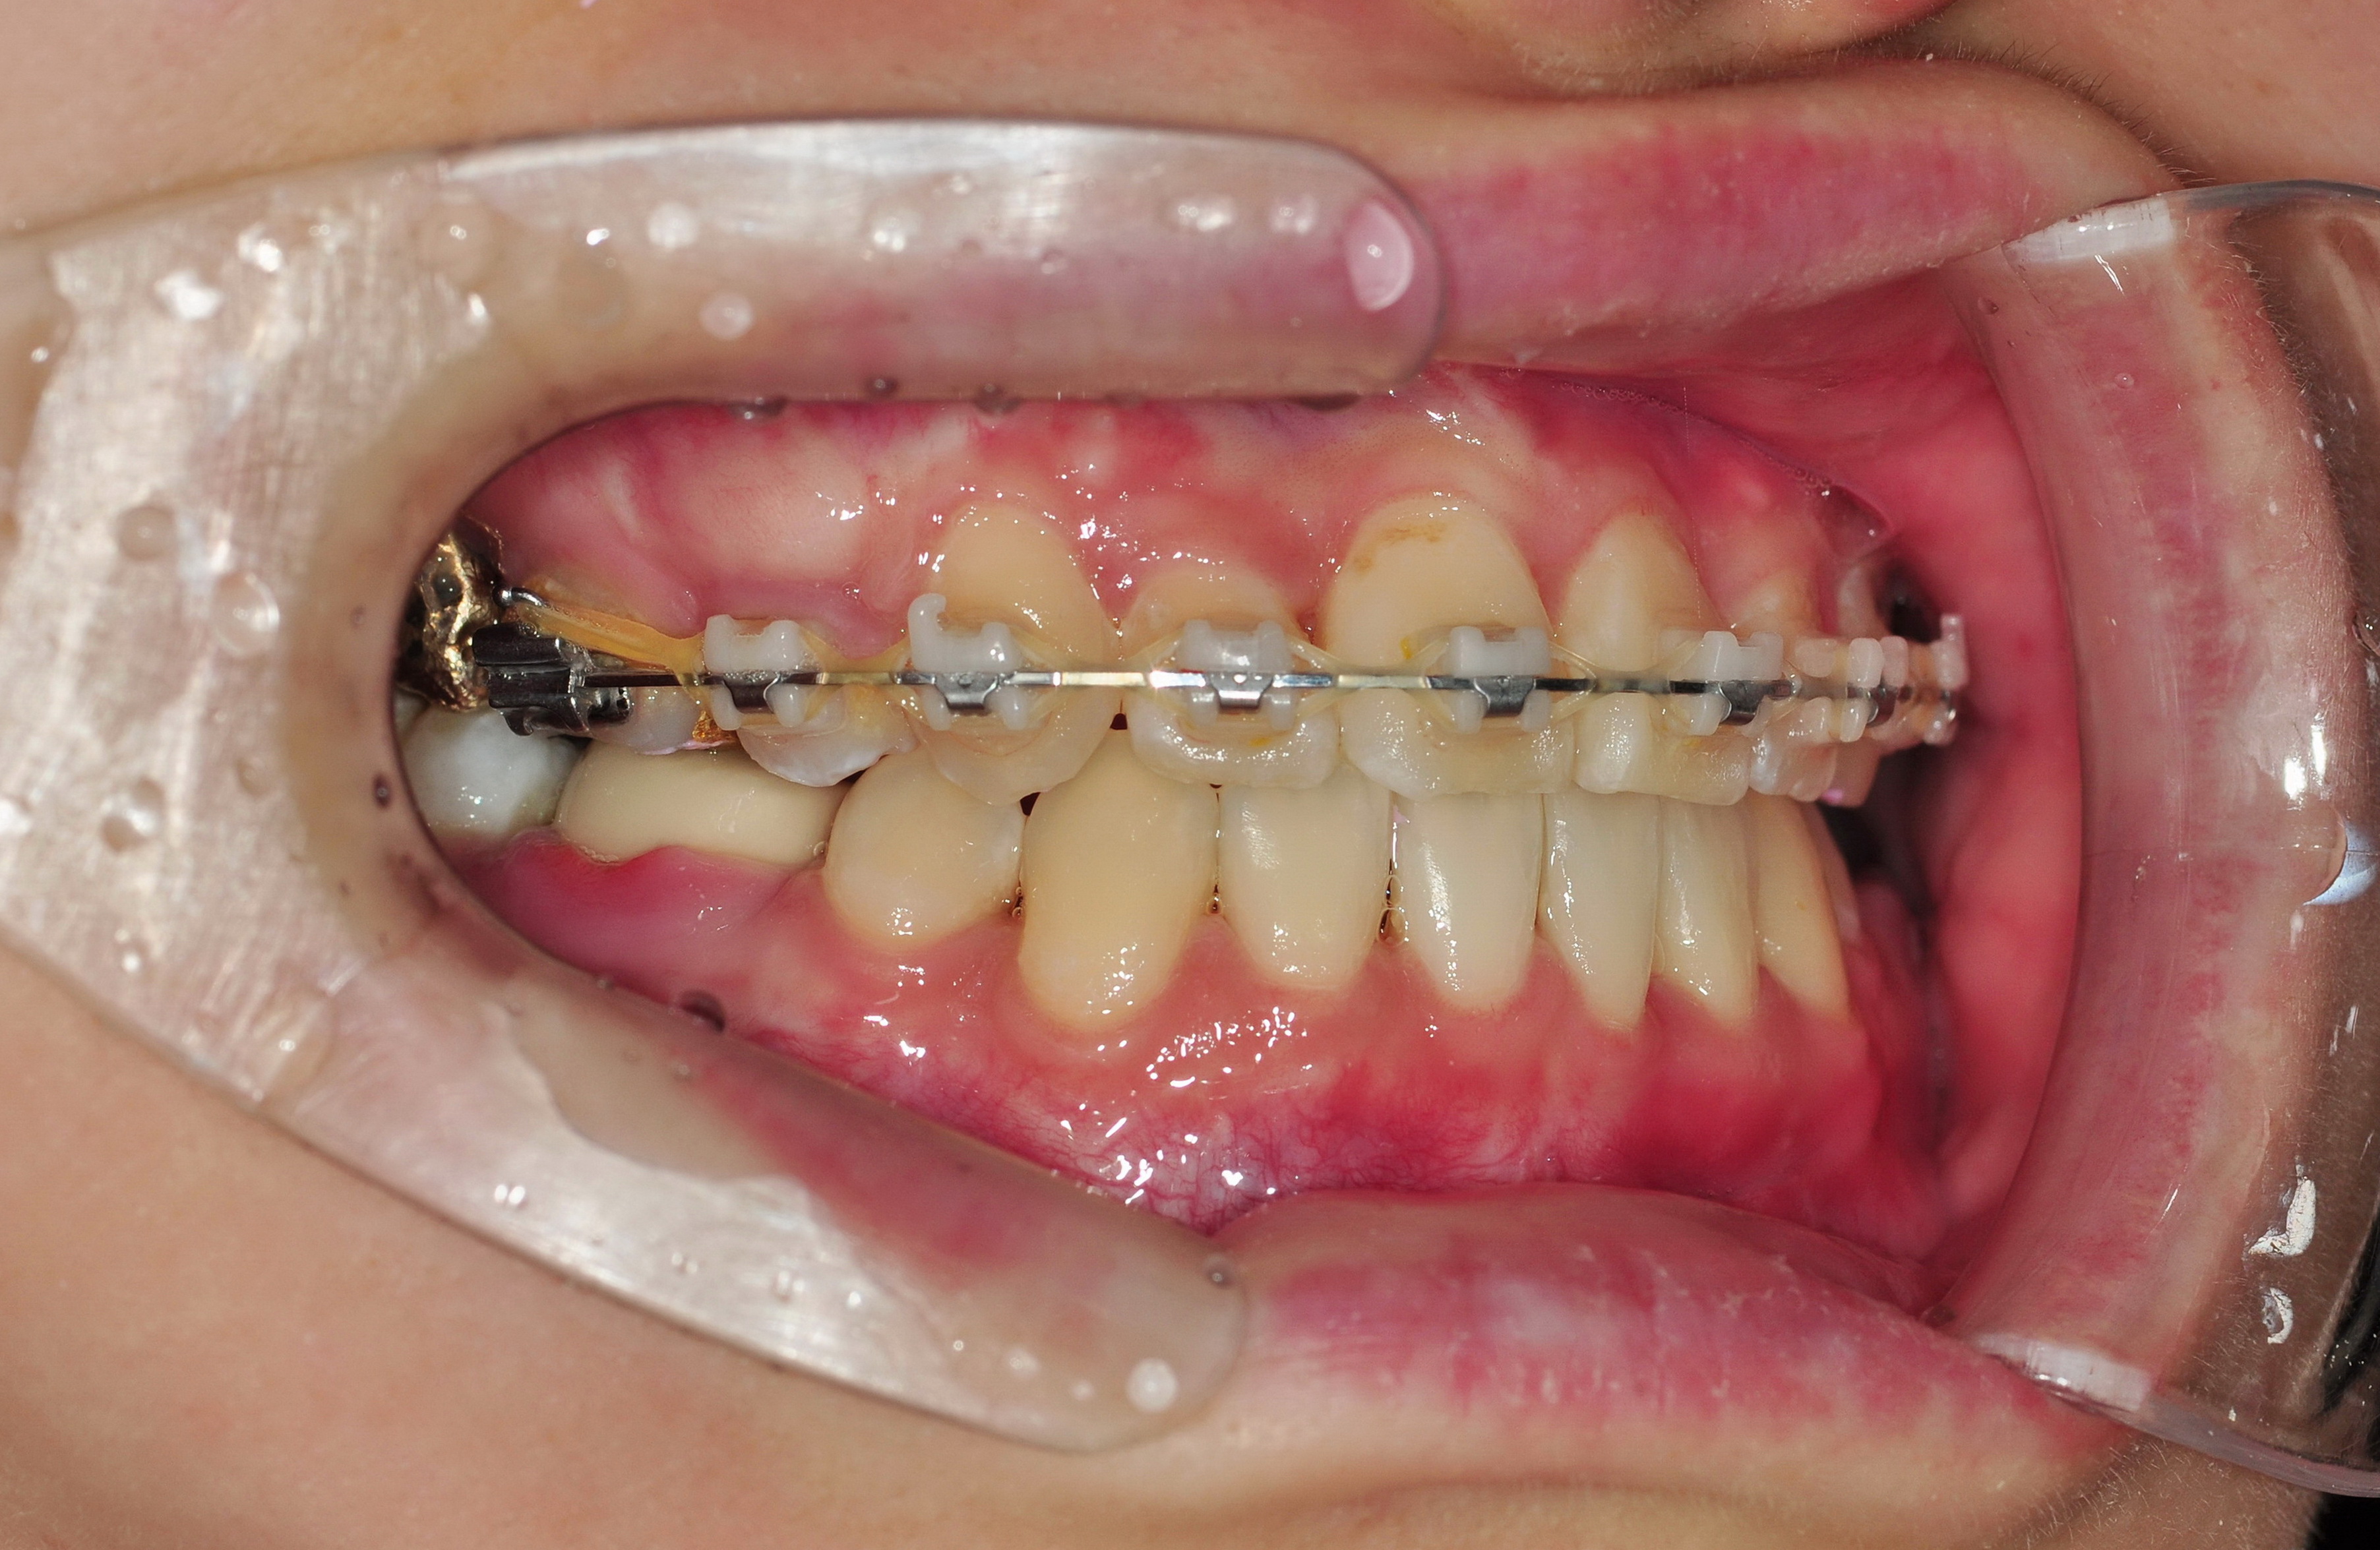

∼ 34. 예쁜 아랫니. ∼

☆★☆ 아랫니 브라켓을 제거했습니다! ☆★☆

아닛! 브라켓 뗄 때가 되니 교합이 아주 완벽하게 맞아!

그동안 고무줄 열∼심히 거셨나 봐요? 교합이 딱 맞아, 딱!

***사진으로 보니 어금니 잇몸에 확실한 염증이 있었네요.

엄청나게 아팠는데 브래킷 떼준 언니가 아무 말 안 해서 내가 예민한 줄 알았음.

수술했던 치과에 검진받으러 갔다가 치료받았습니다.

위 사진 오른쪽 아래 작은 어금니가 도자기로 씌운 치아인데

이런 도자기 치아는 브라켓 제거할 때 깨지는 경우가 있다고 하더라고요.

가지런한데 교합까지 완벽하다는 제 치아를 보세요(아랫니 한정).

뭔가 삐딱하게 찍혔네요. 급하게 찍어서 그렇습니다.